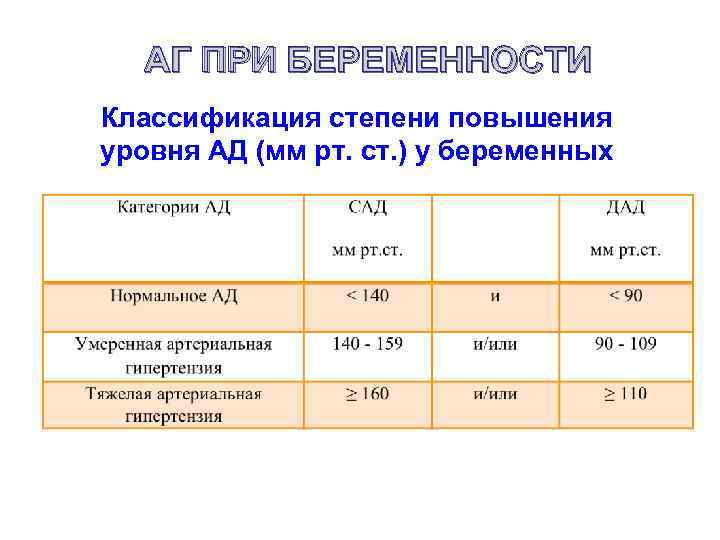

АГ ПРИ БЕРЕМЕННОСТИ Классификация степени повышения уровня АД (мм рт. ст. ) у беременных

АГ ПРИ БЕРЕМЕННОСТИ Классификация степени повышения уровня АД (мм рт. ст. ) у беременных